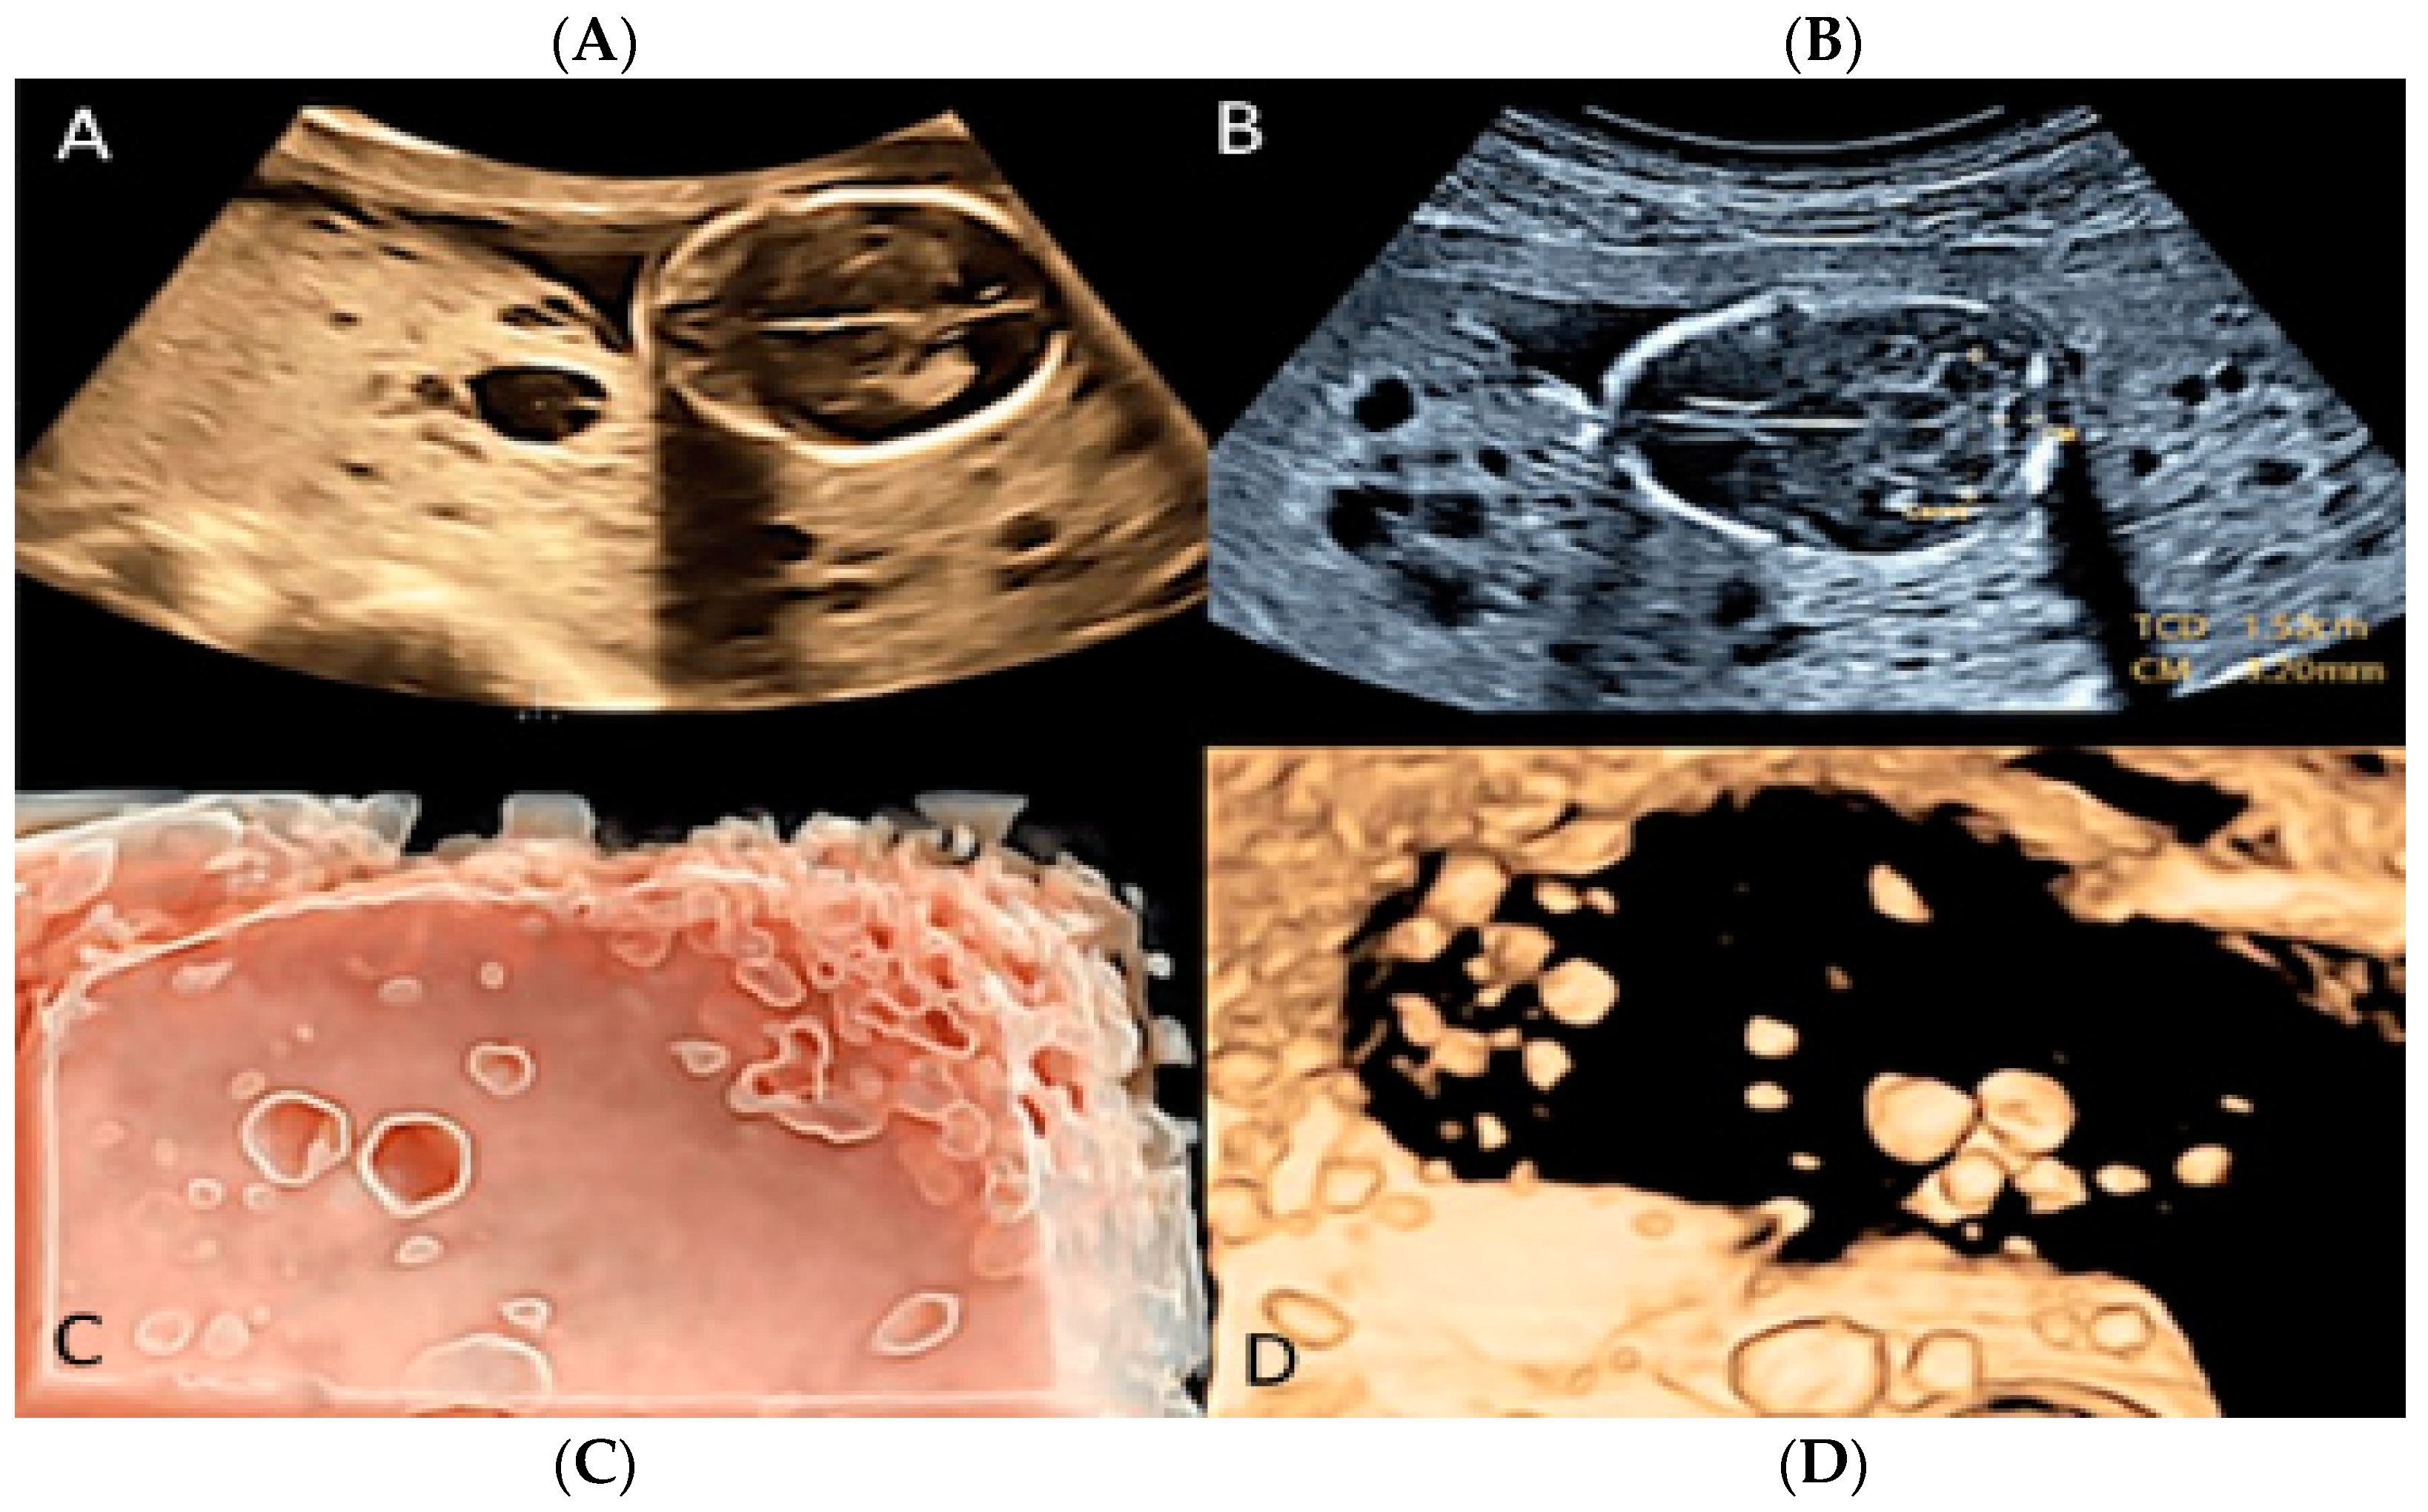

3.1.5. Placental Mesenchymal Dysplasia

- Quintana, R.L.; Baez, C.A.F.; Moraga, F.A.L.; Moraga, E.L.; Zepeda, J.H.G.; Leyva, F.; Manjarrez, R.E.A. Placental mesenchymal dysplasia, a rare pathology. Eur. J. Obstet. Gynecol. Reprod. Biol. 2019, 240, 122–138. [Google Scholar]

- Pawoo, N.; Heller, D.S. Placental Mesenchymal Dysplasia. Arch. Pathol. Lab. Med. 2014, 138, 1247–1249. [Google Scholar] [CrossRef]

- Psarris, A.; Sindos, M.; Kourtis, P.; Pampanos, A.; Antsaklis, P.; Theodora, M.; Chondrogianni, M.E.; Morphopoulos, G.; Loutradis, D.; Daskalakis, G. Placental Mesenchymal Dysplasia: Ultrasound Characteristics and Diagnostic Pitfalls. Ultrasound Int. Open 2020, 6, E2–E3. [Google Scholar] [CrossRef]